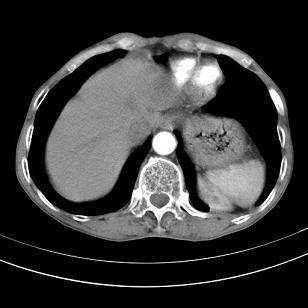

标题: 男,65岁,反复右上腹痛, [打印本页]

标题: 男,65岁,反复右上腹痛,

胃镜提示十二指肠占位